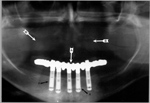

Osseointegrated dental implants with fixed dental bridgework (A); maxillary denture with acrylic teeth (B) |